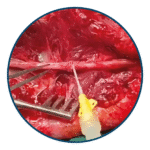

Cirugía, Cirugía Plástica y Craneomaxilofacial, Columna, Hemostáticos, Neurocirugía, Ortopedia

HC Biologics – Synth-X™ Cementos Óseos

• Alta estabilidad mecánica: Supera los estándares ISO 5833 en resistencia a la compresión y flexión.

• Variedad de viscosidades: Disponible en baja, estándar y media viscosidad para diferentes aplicaciones quirúrgicas.

• Opciones con y sin antibiótico: Formulaciones con gentamicina para reducir el riesgo de infecciones.

• Autoendurecimiento eficiente: Rápida polimerización que optimiza los tiempos quirúrgicos.

• Radiopacidad mejorada: Contiene sulfato de bario para una mejor visibilidad en imágenes médicas.

• Baja liberación de monómero: Minimiza efectos adversos en los tejidos circundantes.

• Compatibilidad con sistemas de mezcla al vacío: Facilita su manipulación y aplicación con mínima formación de burbujas.

• Fijación segura de prótesis: Mejora la estabilidad del implante y prolonga su vida útil.

• Reducción del riesgo de complicaciones: Especialmente en casos de infecciones postoperatorias con el uso de versiones con antibiótico.

• Versatilidad en procedimientos quirúrgicos: Aplicable en artroplastias y otras reconstrucciones óseas.

• Optimización de tiempos operatorios: Su rápida preparación y endurecimiento reducen la duración de la cirugía.